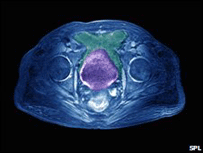

Exame de raio X revelando câncer de próstata

O câncer da próstata é o mais comum entre britânicos